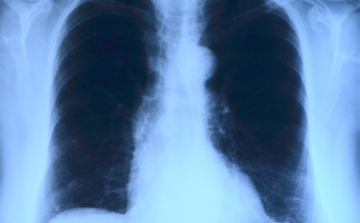

Elvégezték az országban az első tüdőverőér-tágítást

Az országban elsőként a Debreceni Egyetem Klinikai Központjában végeztek tüdőverőér-tágítást - közölte a felsőoktatási intézmény sajtóirodája kedden az MTI-vel.